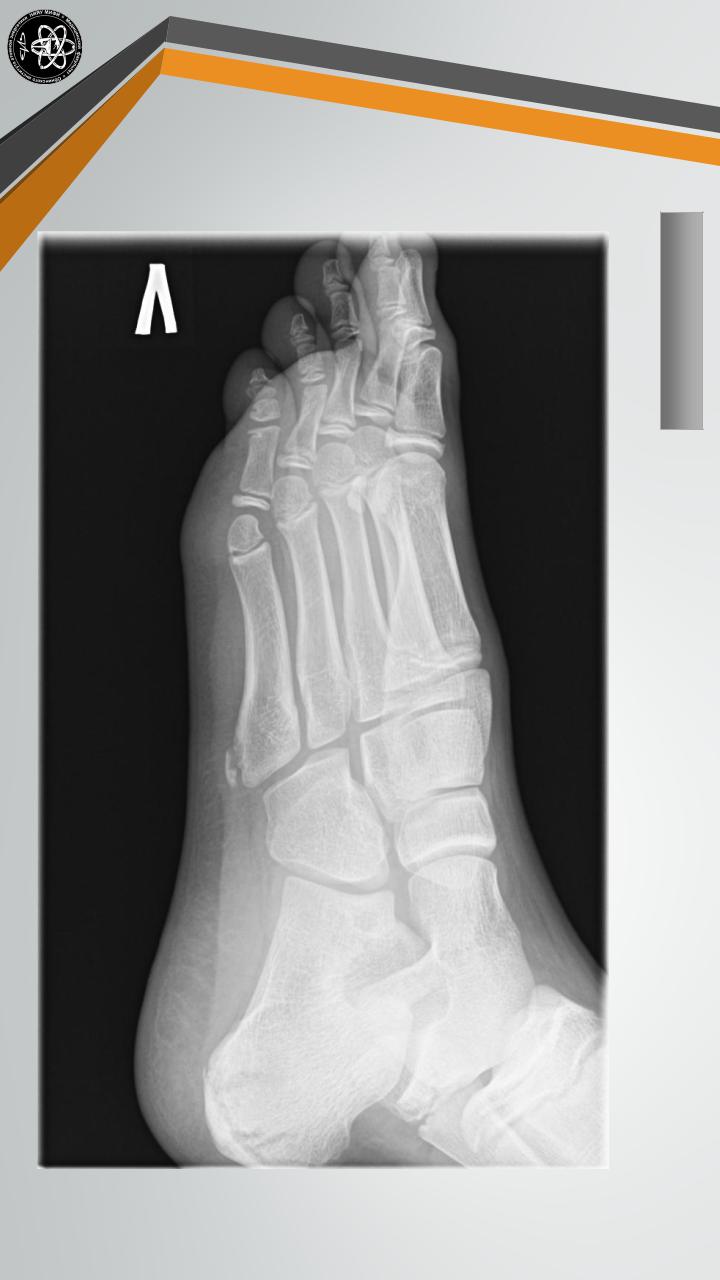

Болезнь Шинца |

Остеохондропатия |

бугра |

пяточной кости. Как правило, |

поражает детей в возрасте 7-14 |

лет. |

Сопровождается |

появлением |

болей |

и |

припухлости. |

Лечение остеохондропатии амбулаторное, включает в себя ограничение нагрузки, электрофорез с кальцием и тепловые процедуры.